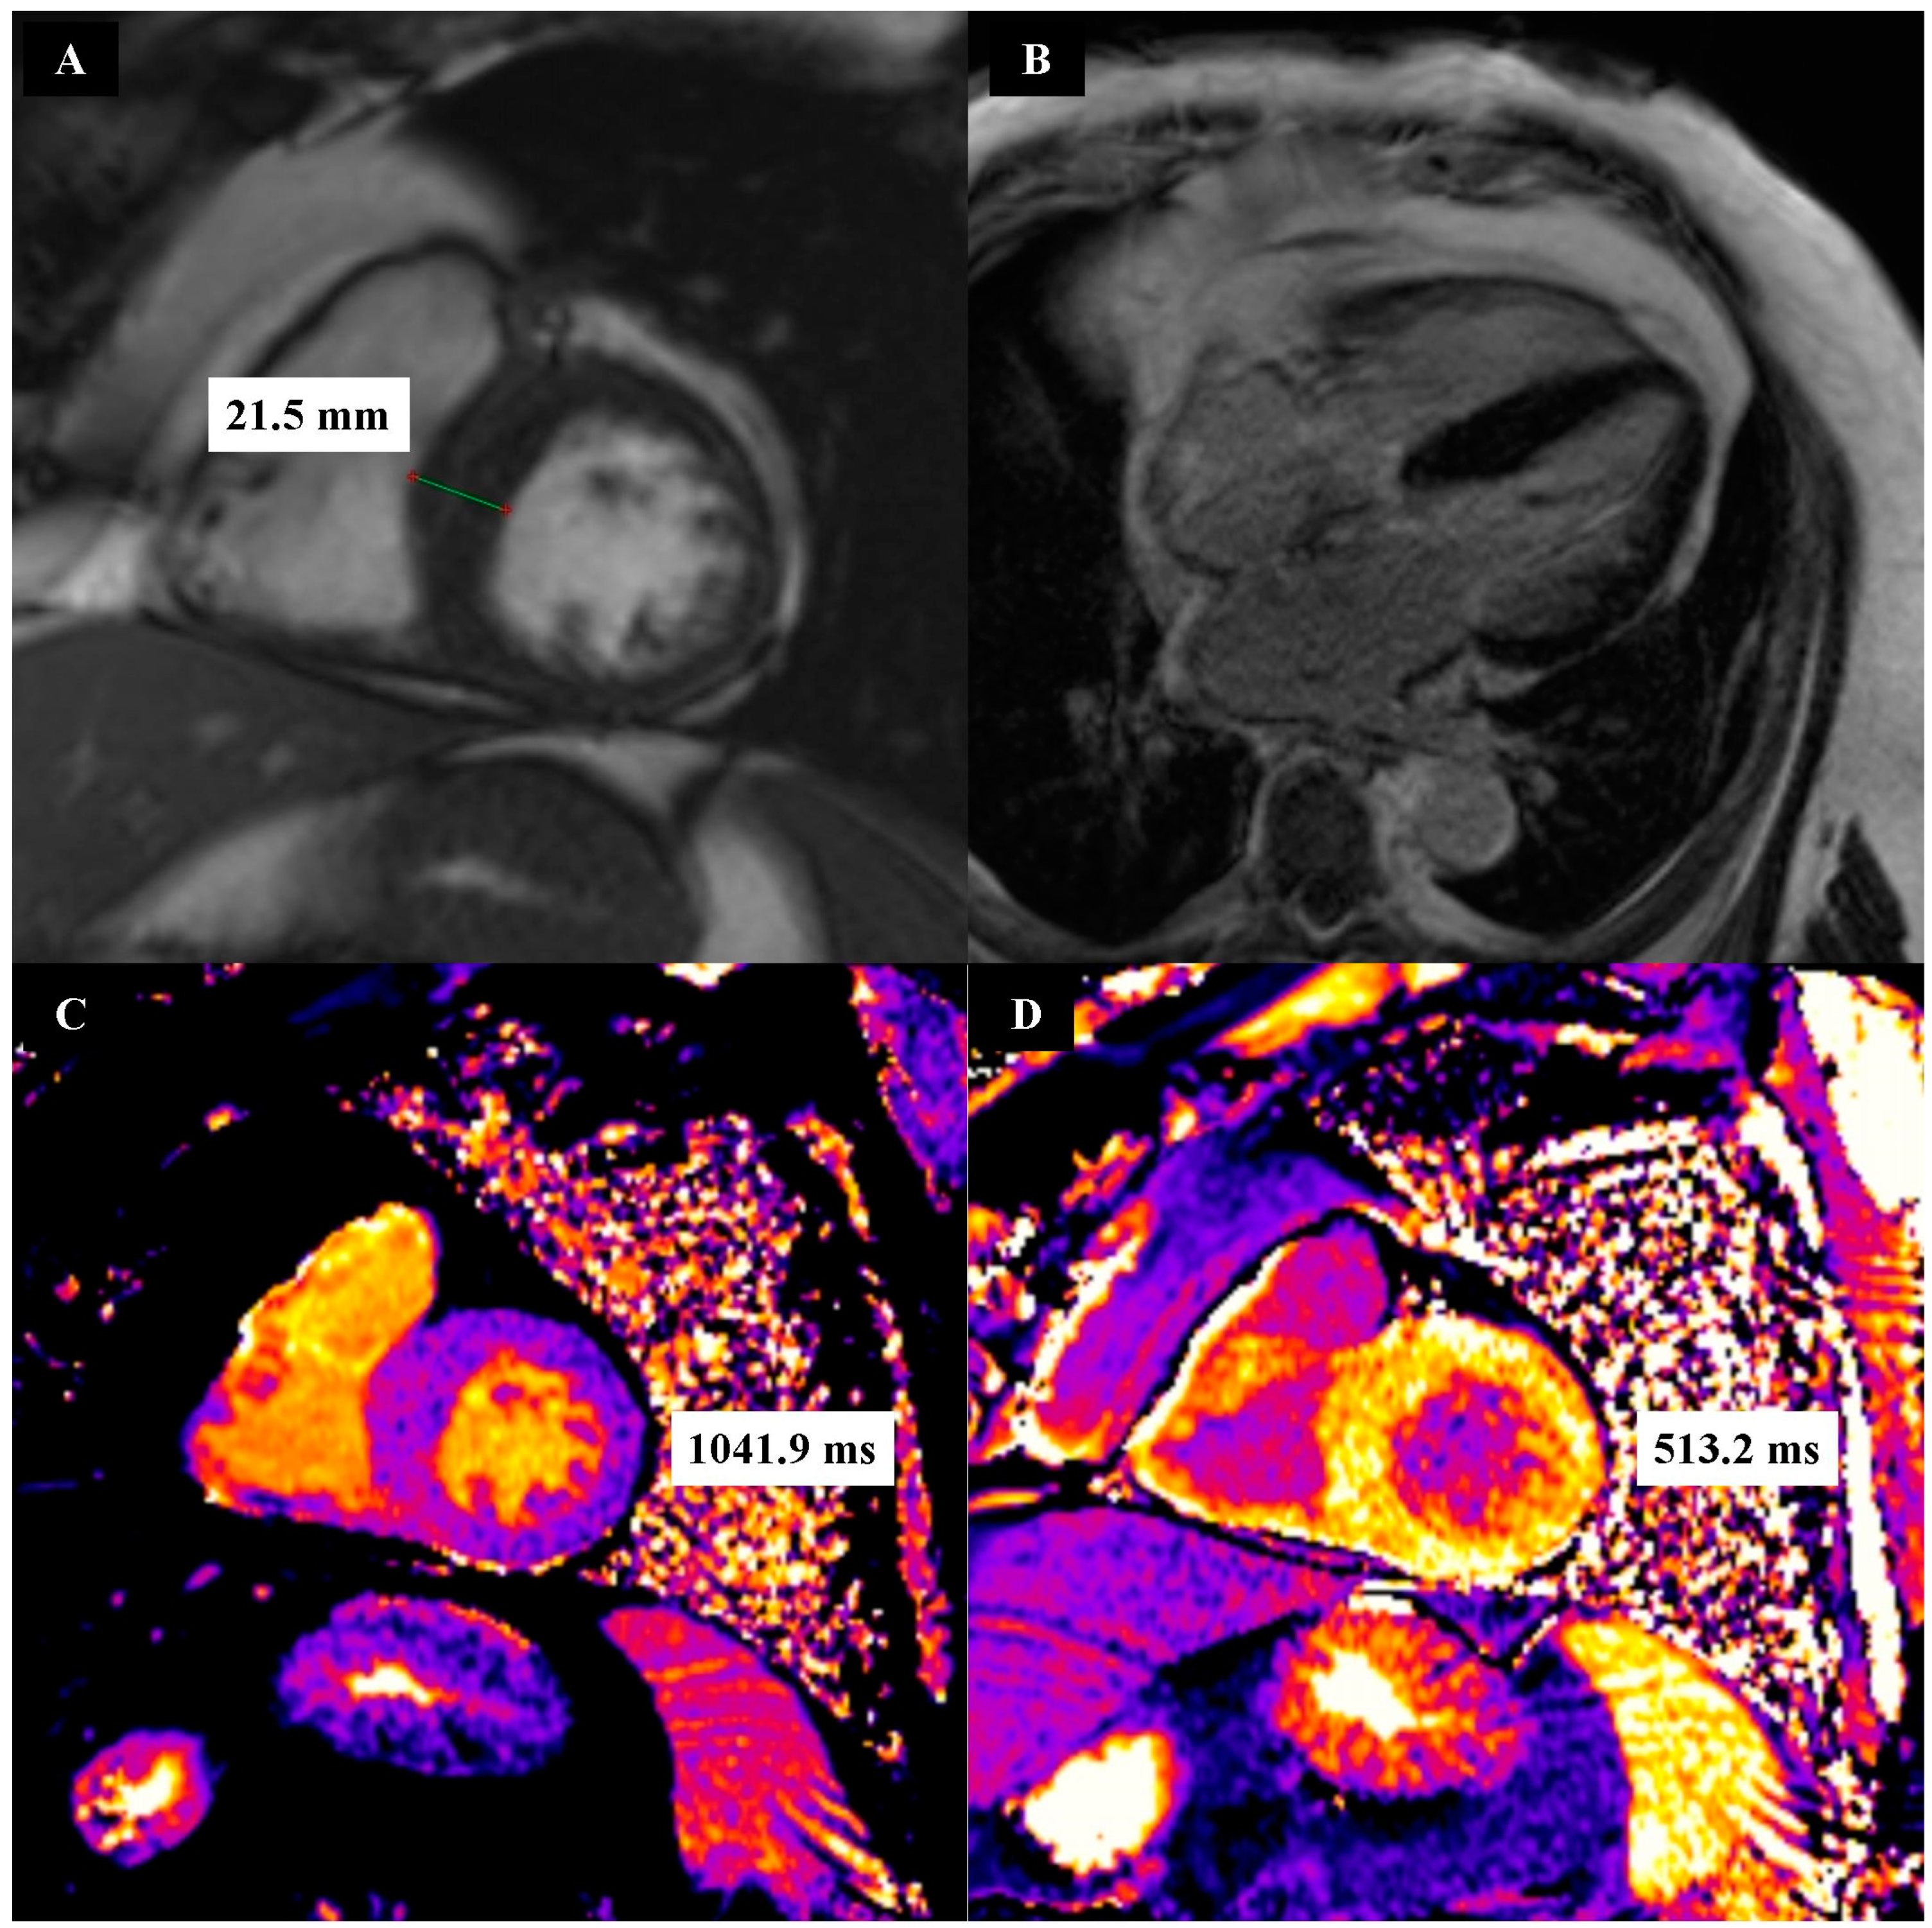

| whole myocardium [ms] a | 1038.15 ± 2.98 | 1031.56 ± 3.65 | - |

| whole myocardium [%] a | 30.23 ± 0.84 | 25.08 ± 0.36 | 0.01 |